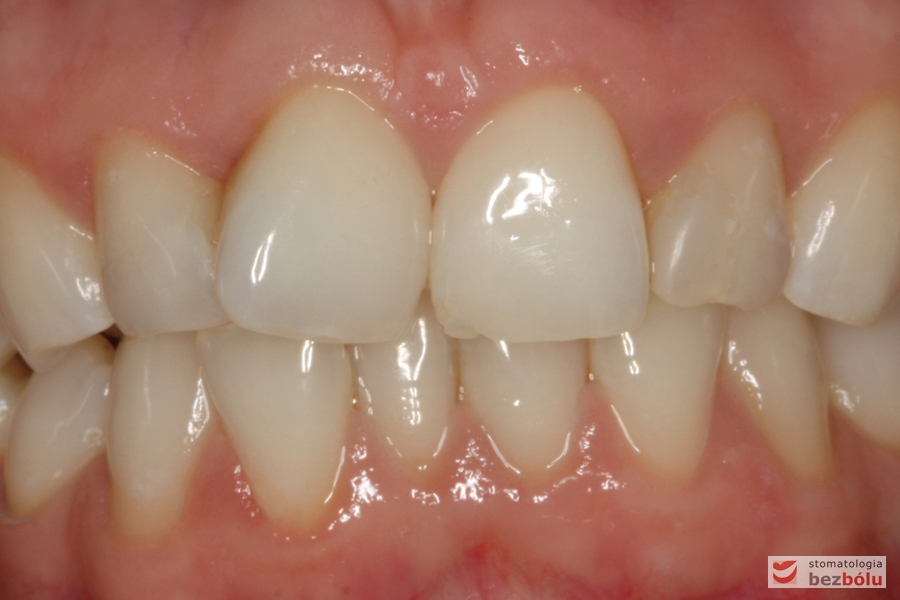

Ostateczne licówki caoceramiczne osadzone na zębach w odcinku przednim

Zmiana relacji długości do szerokości - zbliżenie do normy idealnych proporcji =80%

Zmiana relacji długości do szerokości – zbliżenie do normy idealnych proporcji =80%